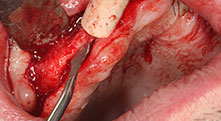

Piezomed B6

The alveolar ridge was split on both sides by piezo surgery (instrument: Piezomed B6). The implants were placed in the same procedure and the peri-implant bone was additionally built up using the GBR technique.